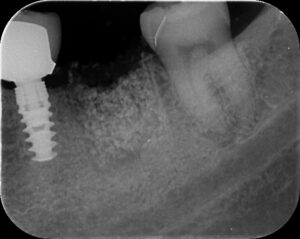

抜歯後2週間で骨増生した症例。